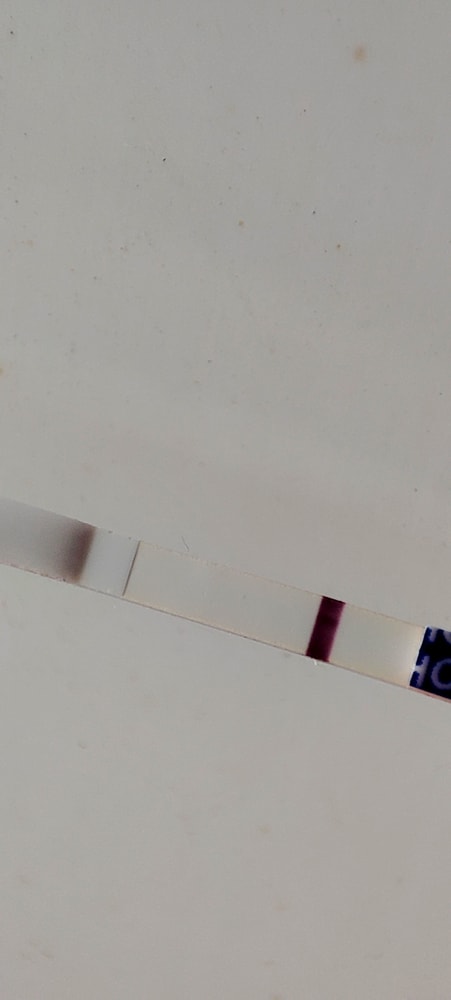

Всем привет, сегодня третий день как я делаю тесты, первый день задержки. Утром делала hometest с чувствительностью 10 - сегодня он кристально чист был, позавчера там была тень, через несколько часов, не успокоившись, сделала itest с чувствительностью 25, на нем тень, снова... Как и три дня подряд на разных тестах (фрау, Хоум). К слову скажу,с первой дочкой тесты были чистые аж до 5го дня задержки, по этому я так усиленно каждый день делаю тесты. Цикл 32 для,фото в комментариях.